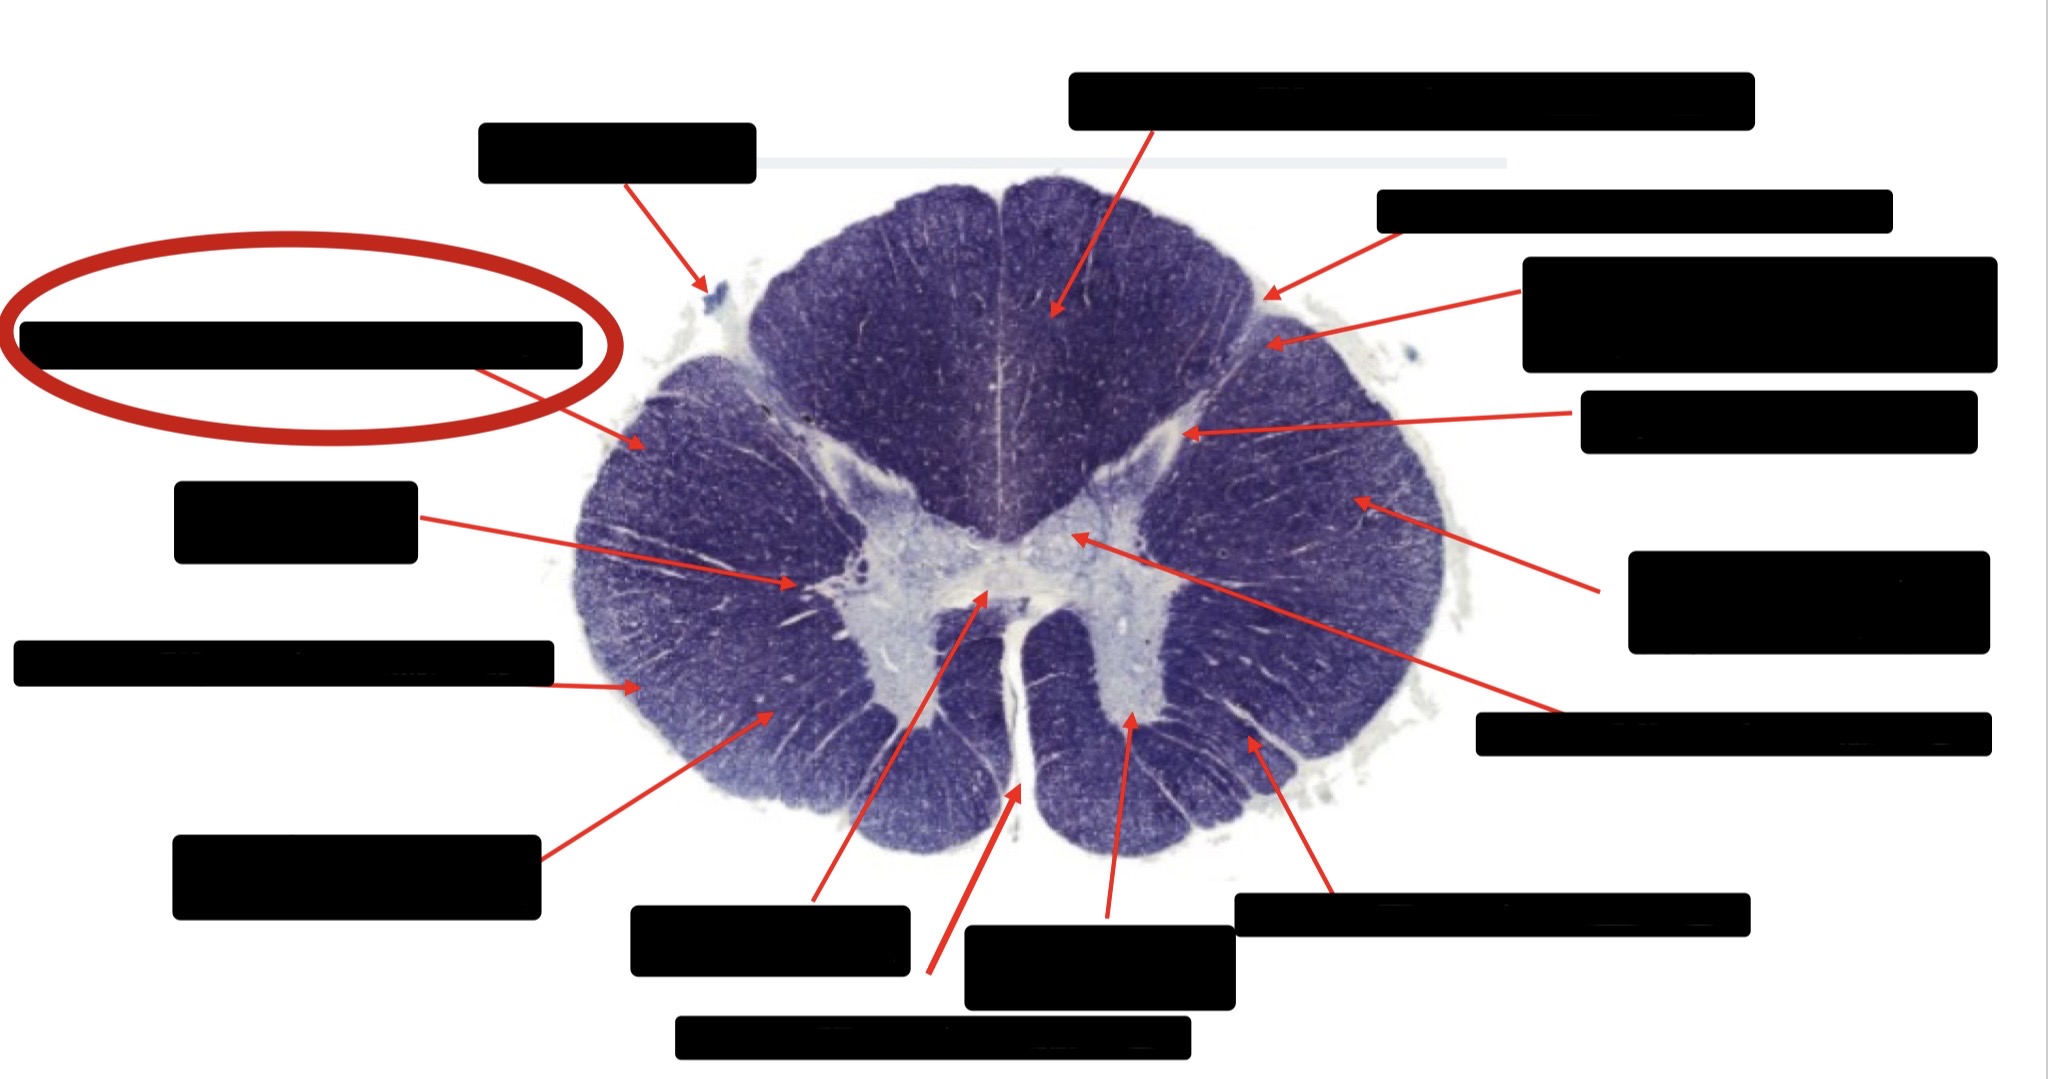

Anterior Spinal Artery

Denticulate Ligament

Ventral Root

Dorsal Root

Posterior Column Fasciculus Gracilis

Large Fiber Entry Zone

Central Canal

Dorsal Rootlet

Lissaeur’s Tract & Small Fiber Entry Zone

Substantia Gelatinosa

Lateral Corticospinal Tract

Anterior Horn Motor Neuron

Spinothalmic Tract

Anterior Horn Motor Neurons